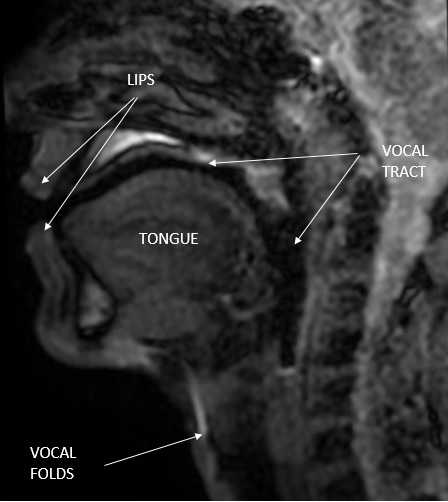

In speech production, we identify a sound source, which is either a reaction to the vibrating vocal folds (in voiced sounds), or a turbulent flow of air due to some constriction of some parts of the vocal tract (in voiceless sounds), or a combination of the two (Image 1). The periodicity in the acoustic waveform is a consequence of the recurring vibration of the vocal folds. This periodicity characterizes the voiced sounds and determines sinusoidal sound waves. The production of most voiceless sounds is the result of turbulent airflow localized in some part of the vocal tract [2].

Image 1 Magnetic Resonance Image (MRI) done by the authors with annotated anatomy of the vocal tract

The shape of the vocal tract, which is modeled as an acoustic filter (filter applied to the sound produced by the source through the property of resonance), can be analyzed to a large extent independently of the source itself.